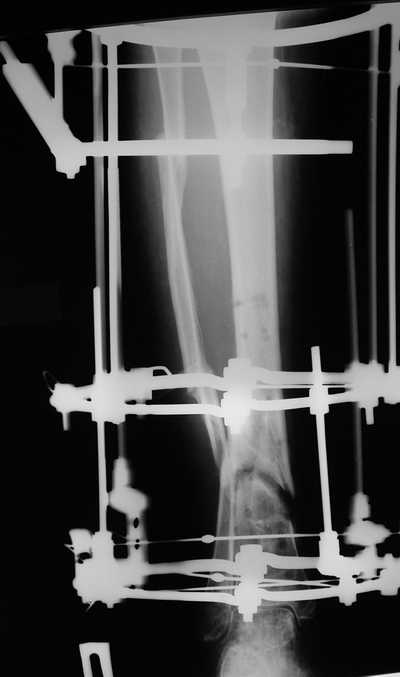

Женщина 46 лет, неудачно лечившаяся по поводу перелома голени в нижней 1\3 сначала в гипсе, поступила через 6 месяцев после остеосинтеза пластиной (рис 1). Имелась деформация в нижней 1\3 голени: варус, антекурвация, наружная ротация, два свища. Удалена пластина, дебридмент мягких тканей,

остеотомия м\б кости, аппарат Илизарова. По рентгенограммам в двух проекциях произведено планирование устранения смещений (рис 2 и 3), между вторым и третьим кольцом установлены 6 телескопических дистракторов Гесапода, данные введены в программу, и далее втечение 10 дней больная подкручивала телескопы согласно выданной компьютером инструкции. По завершению репозиции гексаподные телескопы обратно заменены на обычные штанги от аппарата Илизарова (рис 4 и 5). Еще через две недели забит гвоздь (рис 6, контроль

через 4 месяца).